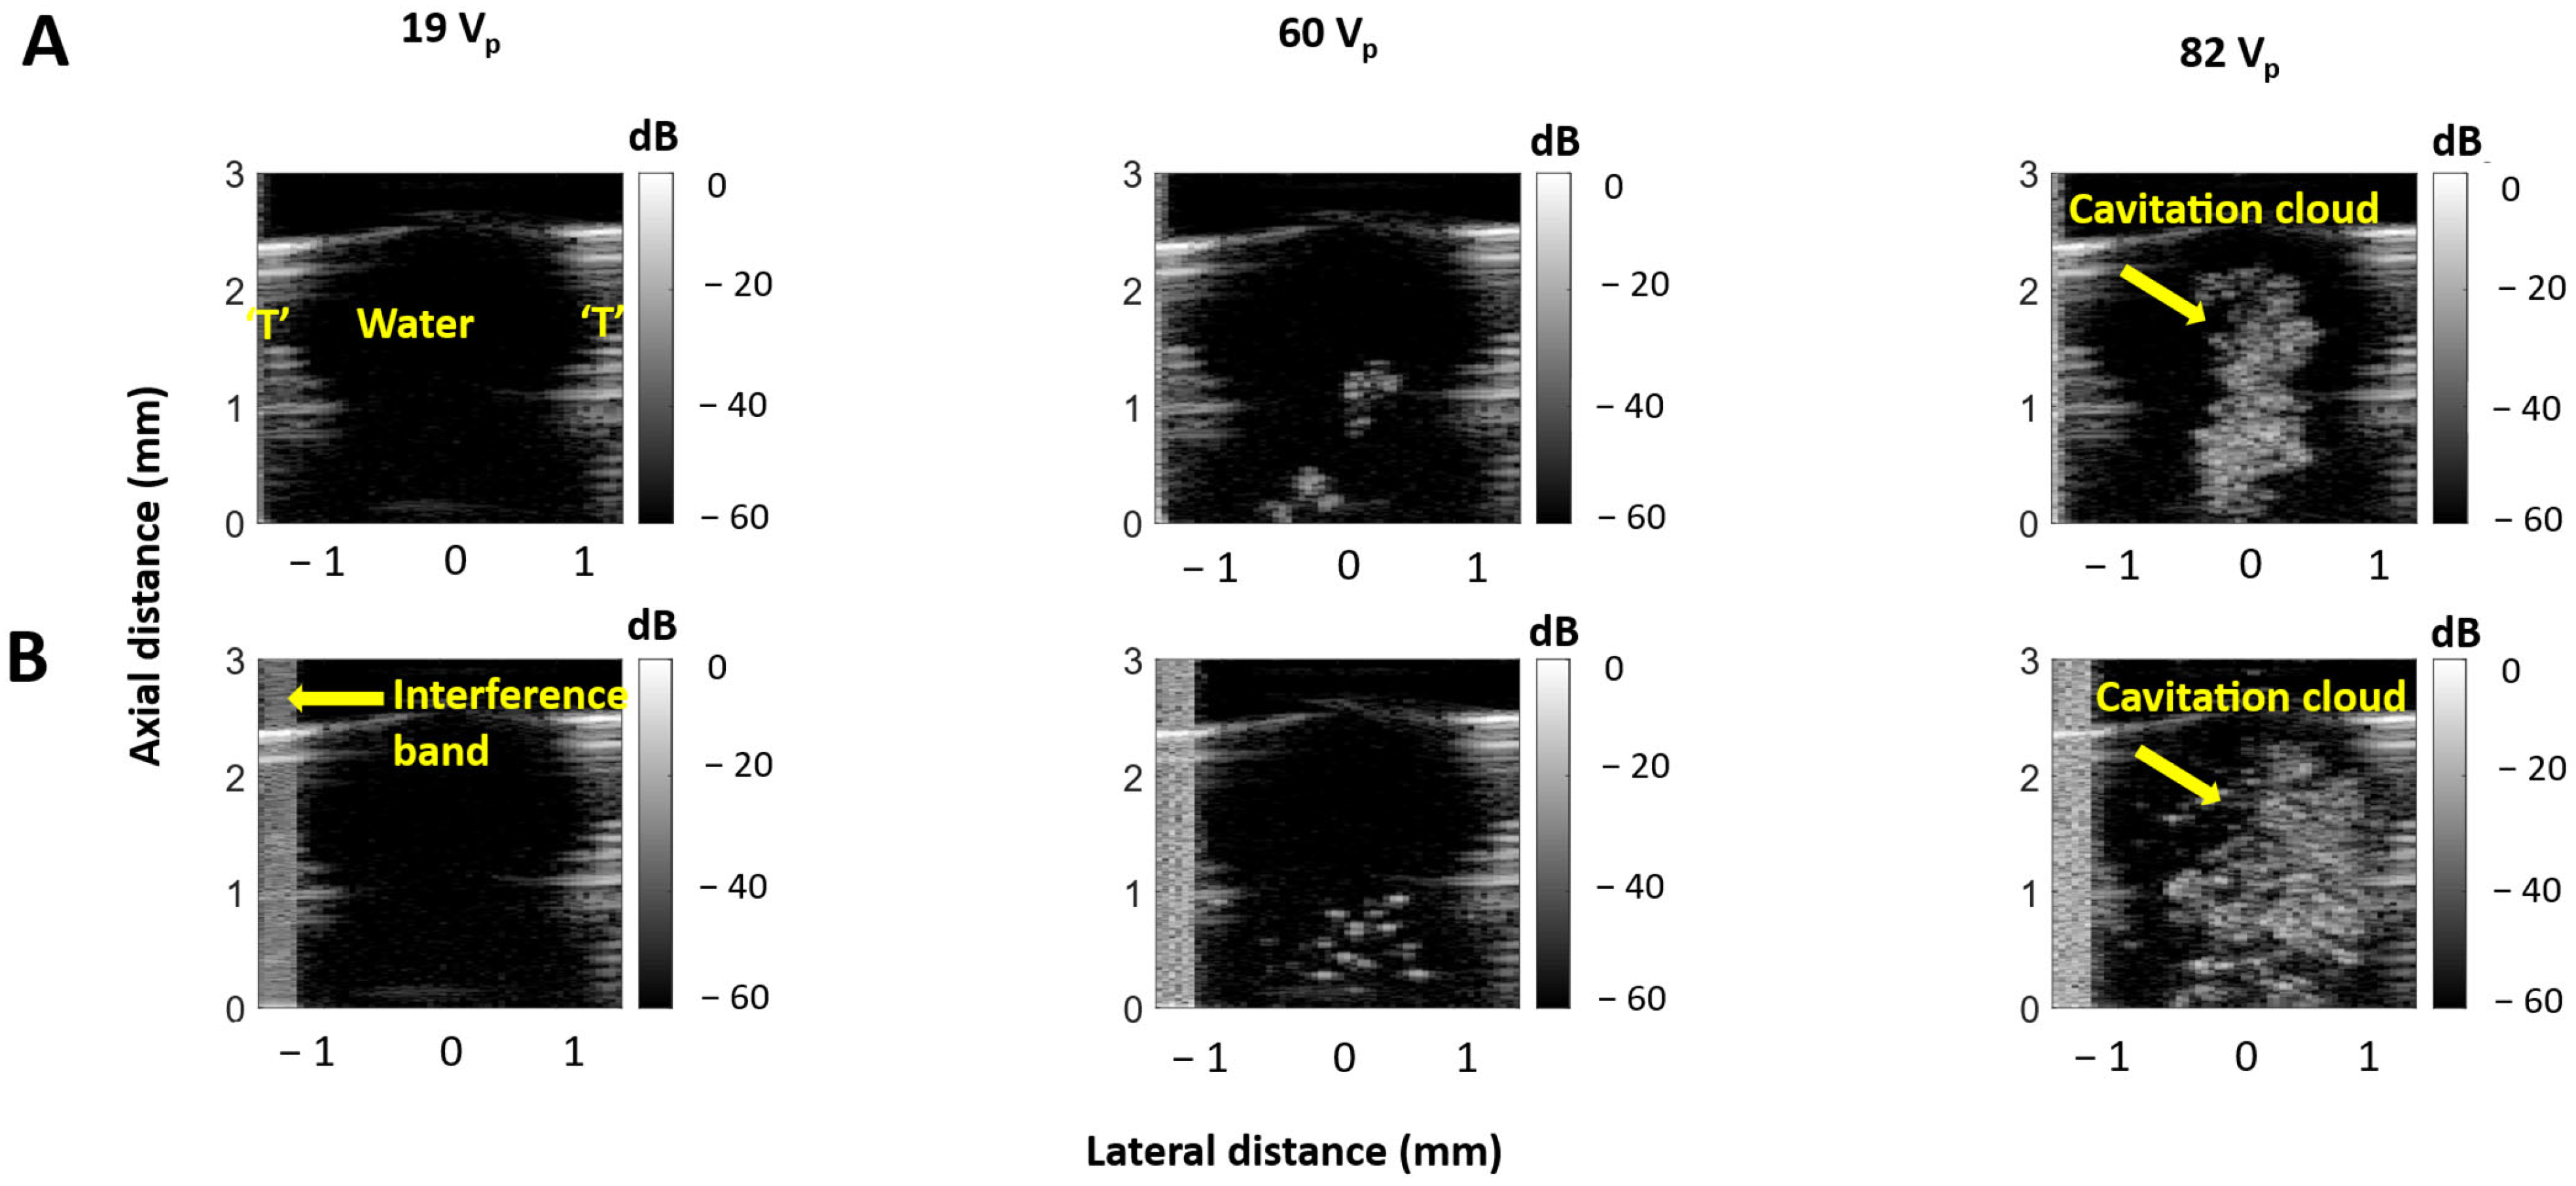

3.2. Cavitation Imaging and Cavitation Probability with Water-Filled Lumen

3.3. Self-Sensing Signals in Water-Filled Lumens

3.4. Self-Sensing Signals During Clot Treatments